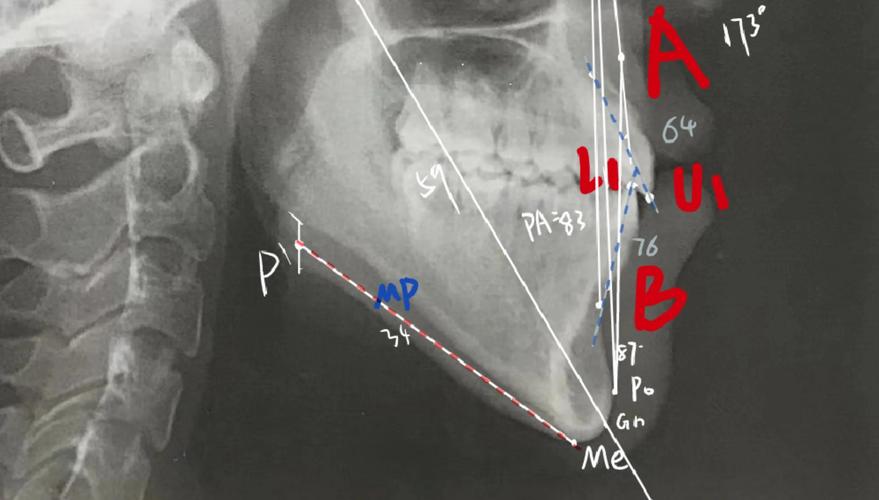

(图片来源网络,侵删)- 操作系统: 查看软件官方文档,确认其支持的操作系统版本(如 Windows 10/11 64位, macOS 版本等)。强烈建议使用官方明确支持的最新稳定版操作系统。